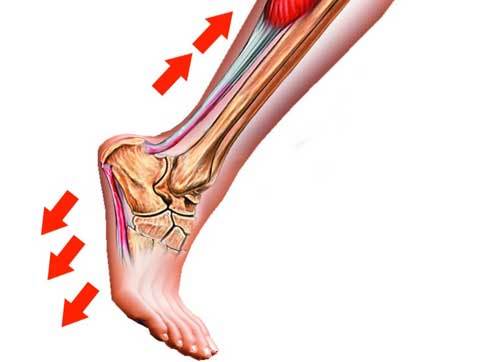

韧带发炎

绝大多数的脚后跟疼痛都是由于韧带发炎引起的。人的脚后跟由33个关节和100多块肌腱和韧带组成,脚底的韧带紧连着跟骨的底端,当人行走时,巨大的牵拉力集中在跟骨下面韧带上一个狭窄的区域内,反复的牵拉摩擦容易导致韧带和骨骼结合部位发炎,造成疼痛。同时,体重也和后跟疼痛有一定关系,一般来说,较胖的人更容易患后跟疼痛。

跟腱炎是影响踝关节的一个常见疾病。跟腱是位于踝关节后方的一条大的肌腱,连接着小腿后方的肌肉群到跟骨,行走、奔跑、攀登等运动都依仗它。

超负荷的运动、频繁在硬性地面如公路上奔跑、爬山等运动造成跟腱过度使用,均容易导致跟腱内的纤维发生慢性损伤,从而引起跟腱炎。在临床工作中,我们遇到的患者中大约有11%的人是因跑步之类的运动损伤引发跟腱炎,跟腱由于血供不充分因而愈合缓慢。

跟腱炎的典型症状是足跟部上方的疼痛,活动后加剧。急性期患者在走路、跑步等运动时出现跟腱疼痛、肿胀,皮肤发红发烫。慢性期患者则会在清晨起床下地时感觉跟腱处疼痛或僵硬,走路(尤其是爬山、上楼时)感觉跟腱处疼痛。

在治疗上,急性期患者应注意休息并采用局部冷敷,垫高鞋跟减少跟腱张力,以及局部外敷药物和口服消炎镇痛药物促进局部炎症消退。此外,患者还可以配合局部超声疗法及电刺激疗法等物理治疗。症状严重者可通过局部封闭治疗缓解疼痛,但注意避免反复封闭引起跟腱断裂。保守治疗6月以上症状仍未减轻的患者可以考虑手术治疗,切除止点部炎性组织、滑囊和退变的跟腱及增生的跟骨后上结节。